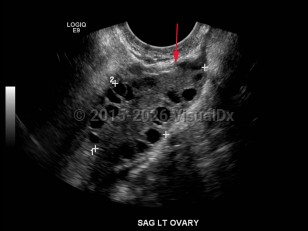

Polycystic ovarian syndromePolycystic ovarian syndrome

Krukenberg tumor

Cervical cancer